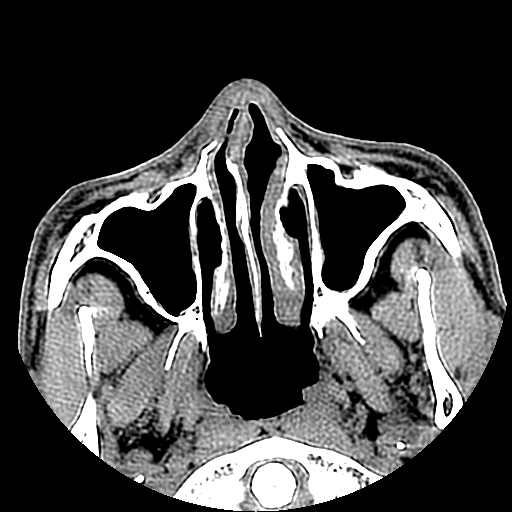

以下是引用liaoqiang在2008-7-16 21:15:00的发言:[br]右侧鼻骨骨折

以下是引用zxd95在2008-7-16 21:39:00的发言:[br]右侧上颌骨额突骨折。[br][br][br][br]